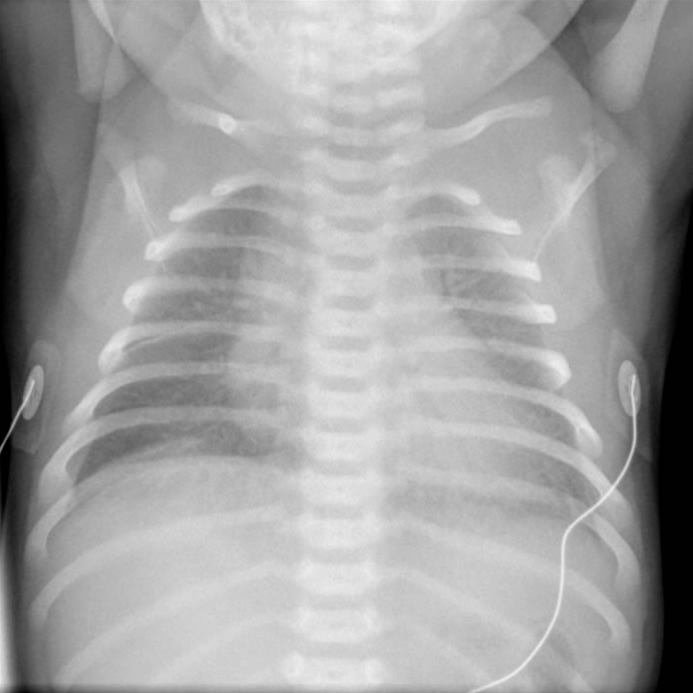

Forbigående takypnø, røntgen

• Kaldes også transitorisk tachypnoe eller "wet lungs"

• Rtg. thorax viser diffuse lidt vattede parenkymatøse infiltrater, en "våd silhuet" omkring hjertet, eller intralobær væskeophobning